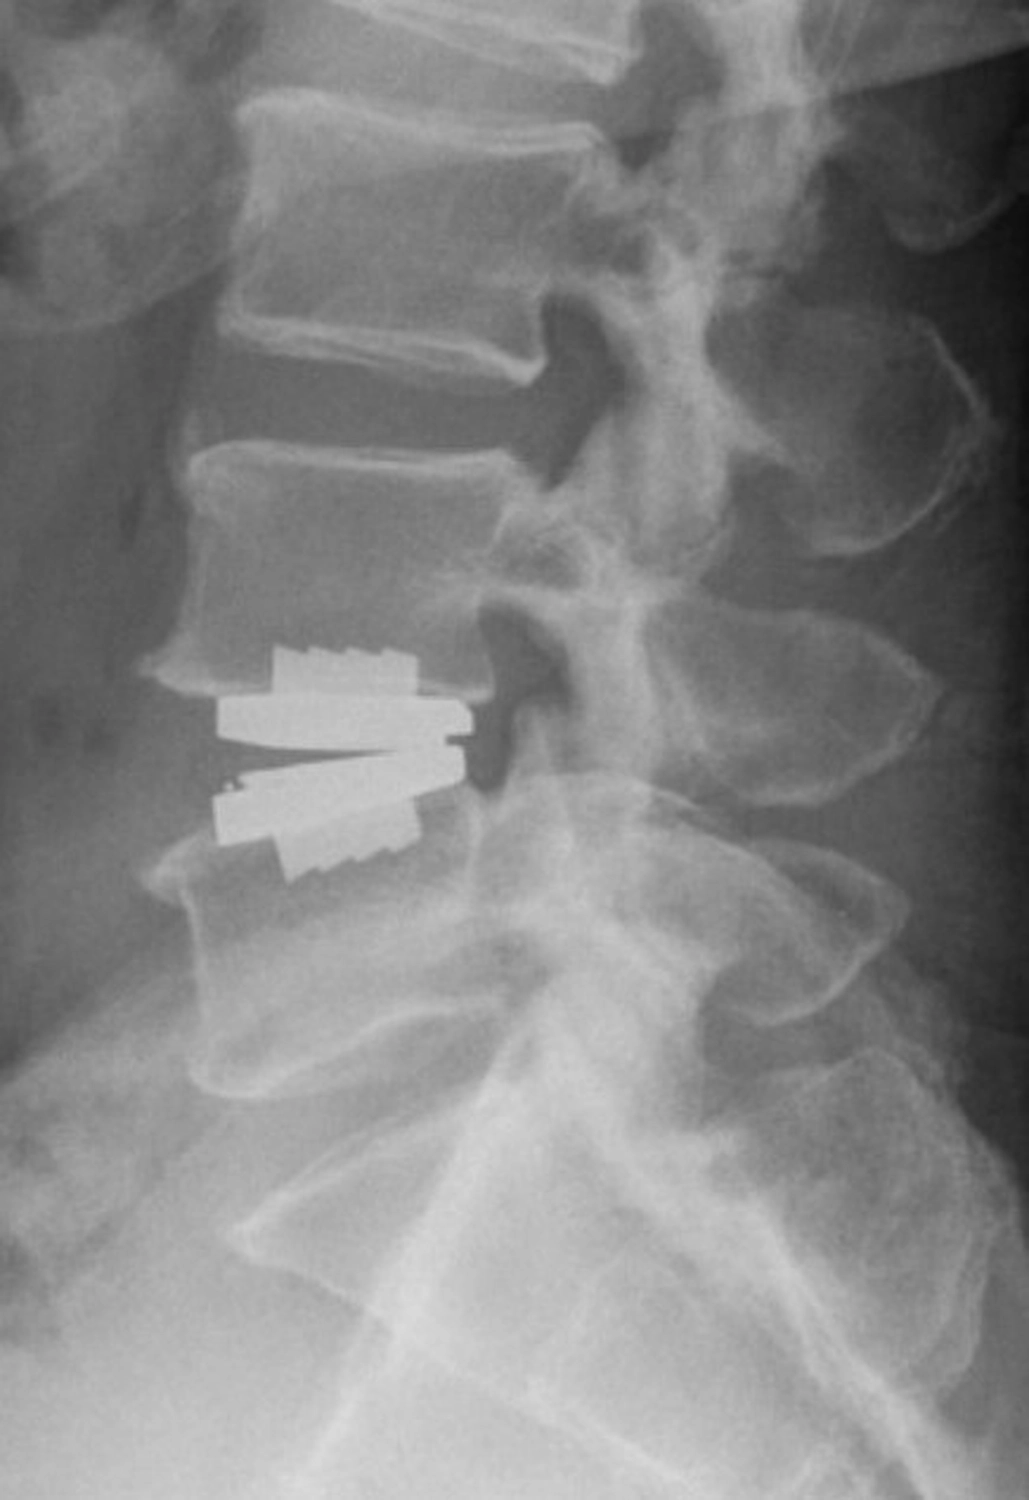

Dieser Prozess beginnt im Regelfall mit einer umfassenden Beratung und Auswertung der vorliegenden Befunde. Unser wirbelsäulenchirurgisches Spektrum ist breit aufgestellt – von minimalinvasiven Methoden bis hin zu komplexen rekonstruktiven Eingriffen beherrschen wir ein breites Portfolio an Eingriffen. Dieses wird durch technische Unterstützung – vom Operationsmikroskop bis hin zu intraoperativer Navigation – abgerundet. Dabei ist unser Anspruch, die Patienten bestmöglich zu beraten und zu informieren. Zudem verfolgen wir ein sehr stringentes Komplikationsmanagement, um mögliche Komplikationen so schnell wie möglich zu erkennen und erfolgreich zu behandeln.